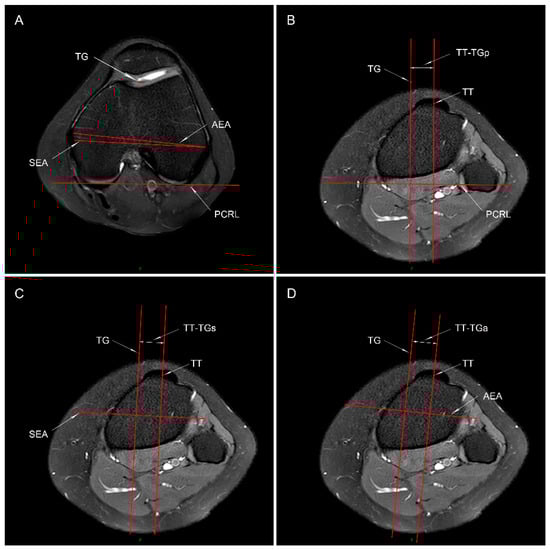

2.3.1. TT-TG Distance